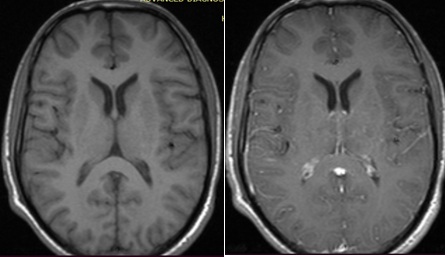

On neuroimaging, MRI cervico-thoracic spine showed T2 hyperintense lesion extending from the lower cervical to the mid-thoracic cord with minimal cord expansion, with no post-contrast enhancement, likely due to inflammatory demyelinating aetiology. (Figure 1 & 2) MRI Brain with contrast done in this patient, was reported as an essentially unremarkable study with no evidence of demyelinating plaques or any other significant abnormality (Figure 3).

Figure 3: MRI Brain Axial view, plain (left) and with contrast (right) showed no contrast enhancing lesion reported as unremarkable study.